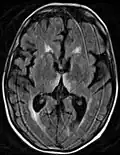

-

Axial MRI FLAIR image showing hyperintense signal in the mesial dorsal thalami, a common finding in Wernicke encephalopathy. This patient was nearly in coma when IV thiamine was started, he responded moderately well but was left with some Korsakoff type deficits. -